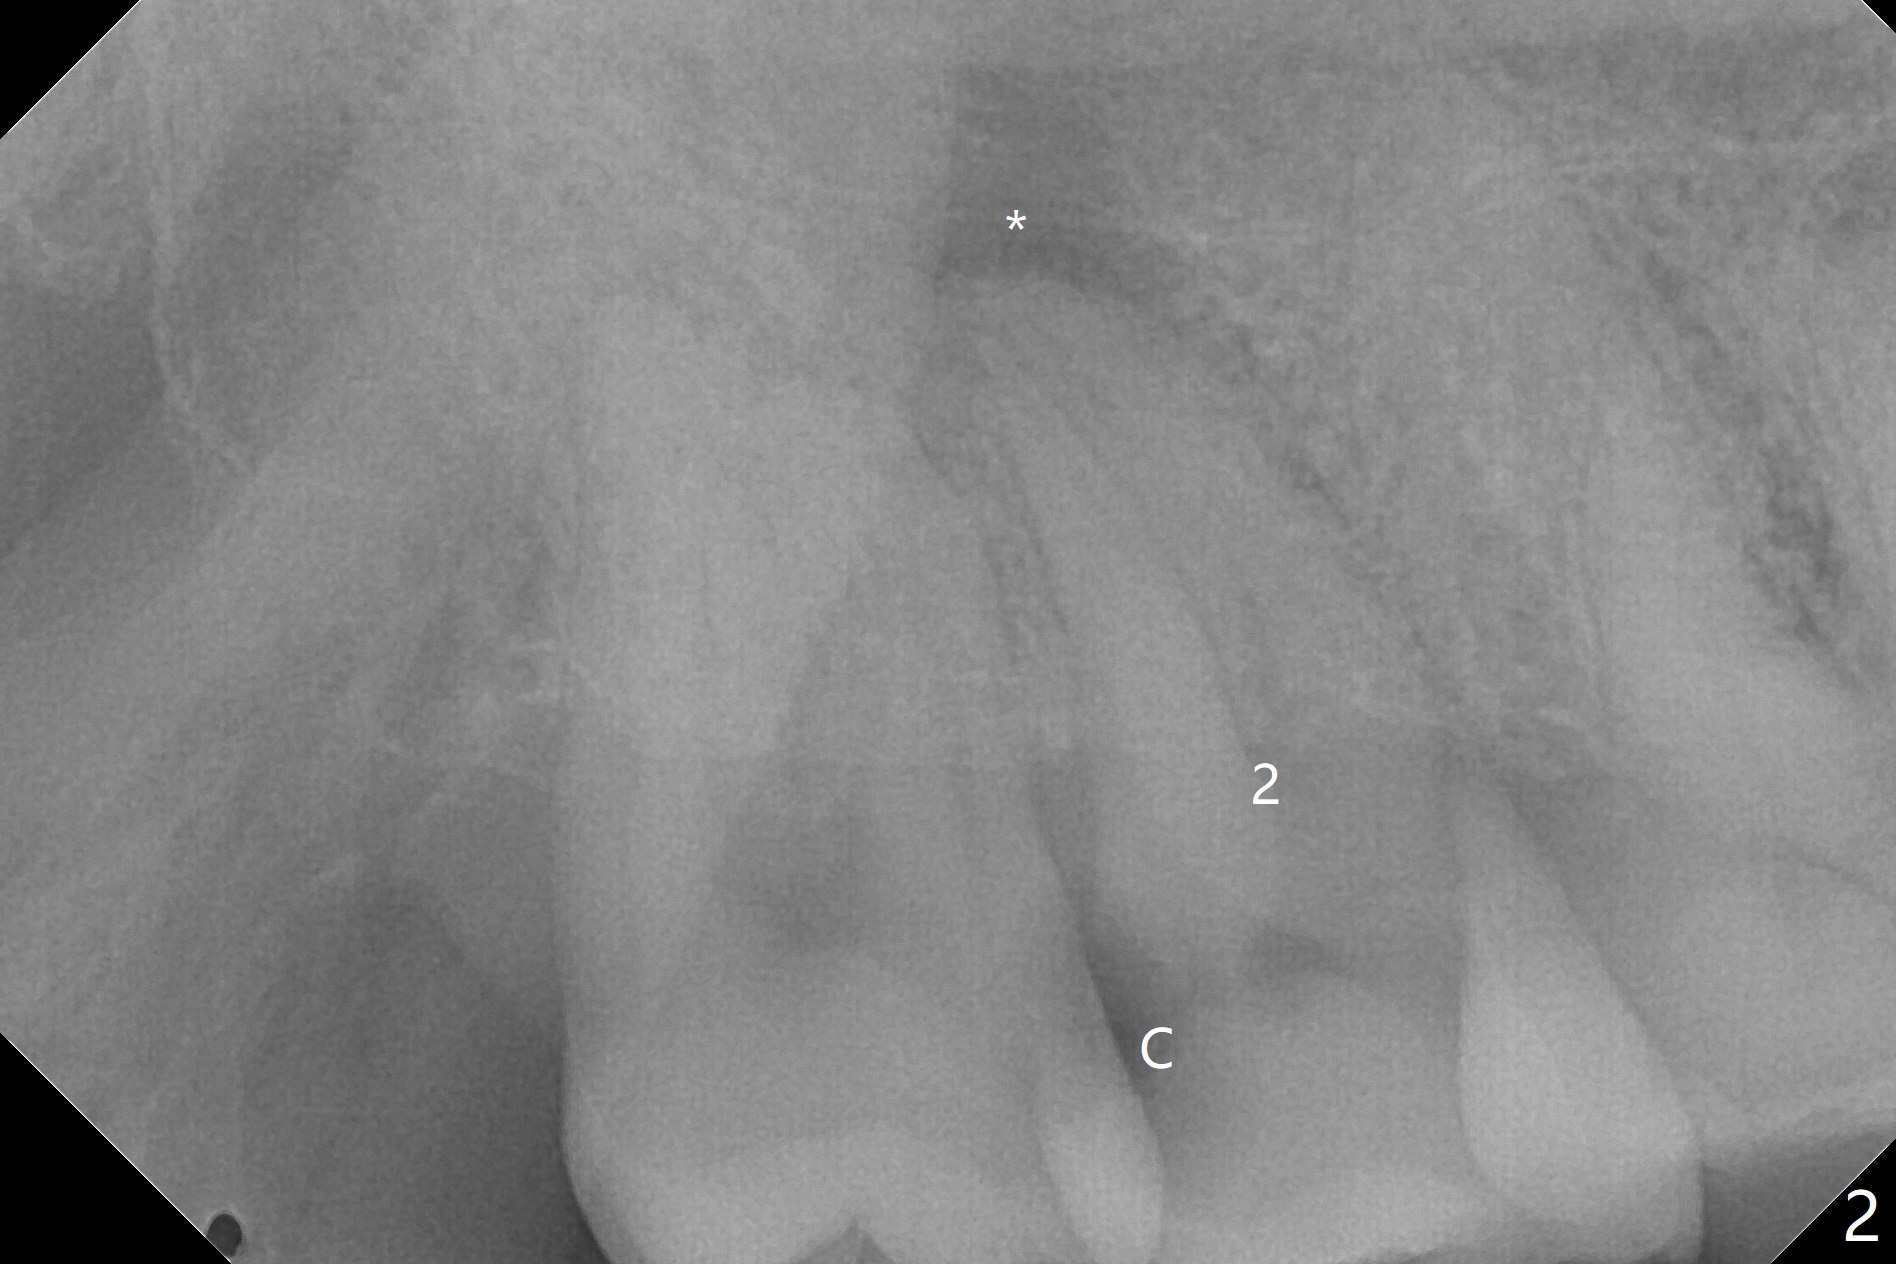

A 62-year-old man has palatal abscess with deep pockets (Fig.1 A) at tooth #2 with DO caries (Fig.2 C). The patient agrees with extraction and bone graft. Preop CT shows the palatal (P) wall defect and buccal (B) socket perforation (Fig.3 *). It should be easy to do sinus lift with the thick sinus membrane (M). To maximize hard tissue regeneration, GEM21S is used to hydrate ground cortical chips (particle size: 125μm – 850μm)) and cortical/cancellous allograft (.5-1 mm) for socket preservation (Fig.4 G) and sinus lift in the buccal socket (^). Due to swollen soft tissue and overpacking, the bone height increases (Fig.5 arrow). The socket opening is closed with GEM Cap and Perio Glue as well as perio dressing.